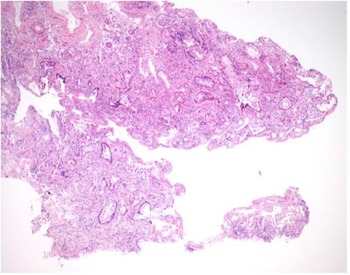

The mucosal biopsy sections measured 8 mm × 4 mm in maximum dimension. There was extensive loss of surface epithelium (Figure 2), with no associated surface fibrin or inflammatory exudate (Figure 3). The architecture of glands in the lamina propria was maintained. A minimal chronic lymphocytic inflammatory infiltrate was present (Figure 2). No eosinophils or mast cells were identified.

Fig. 2. Low power stain shows mucosa devoid of surface epithelium. There is mild chronic inflammation, but no evidence of acute inflammation. (H&E; ×25)